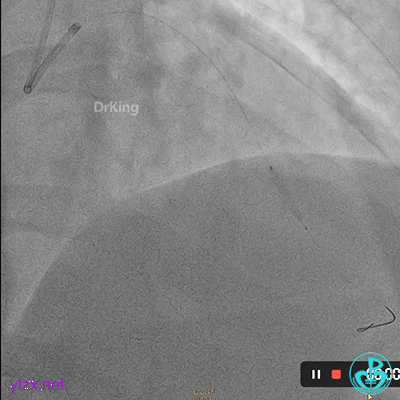

06 8天后复查冠脉造影

RCA粗大近中段瘤样扩张明显,中段血栓影消失,左室后支显影,后降支近段可见造影剂滞留, TIMI血流3-级。